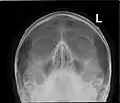

![]() مخطط أمامي للجيوب الجانبية الأنفية | |